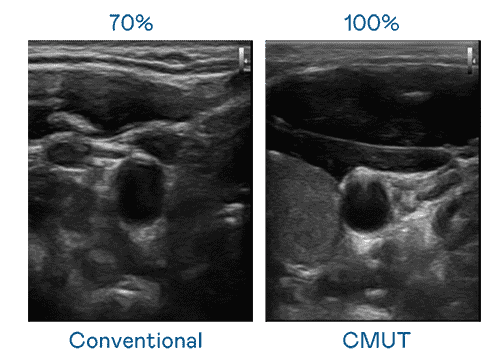

CMUT 技术是一种用电容式微机电元件来产生超音波讯号的技术。。。。与传统 PZT 压电式技术相比,,,,CMUT 频宽增加 30%,,,更宽频的超音波讯号让影像解析度大幅提升,,是实现高影像品质医疗超音波扫描、、、、促进精准医疗发展的关键技术。。。

大频宽带来超清晰影像

超音波影像的解析度高低,,,首先取决于探头能发出的讯号频宽。。z6mg·人生就是博 CMUT 可提供高清晰的超音波讯号,,提供高频宽、、、、高灵敏度、、、影像纹理细节更高的超音波影像,,,协助医护人员缩短影像判读时间及利用精准的医疗影像进行诊断。。。